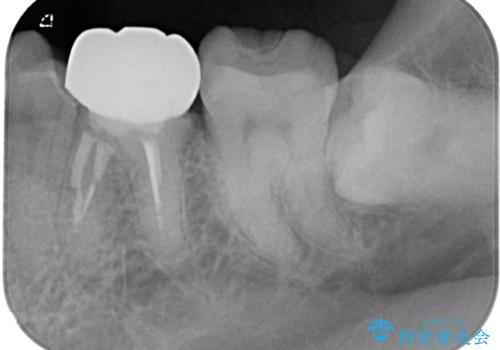

詰め物の範囲が大きいためフルジルコニアクラウンによる補綴治療を行いました。

拡大鏡視野下で詰め物、虫歯を除去しフルジルコニアクラウンに適切な形に整えました。

型どりの際には唾液も多く舌も動いてくるため個歯トレーにて精密印象を行っています。

仮歯に変える前に左下の埋伏親知らず抜歯を行っています。